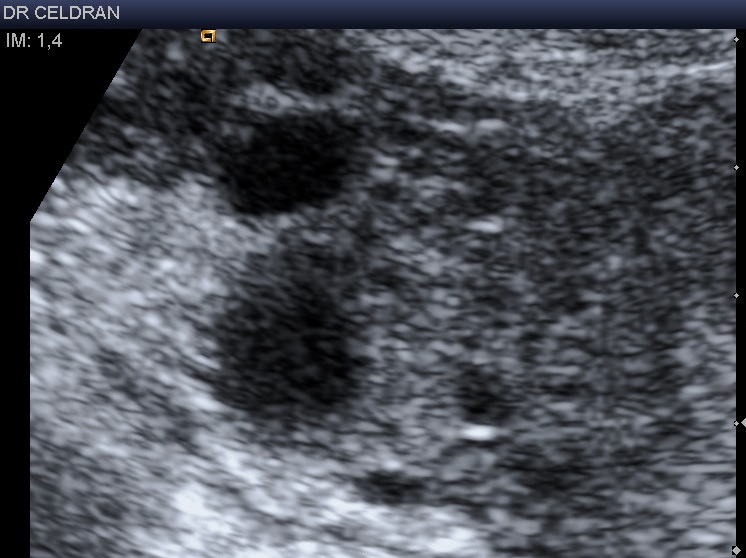

Autre patiente : ovaire droit également visualisé au moyen d’une sonde linéaire haute fréquence